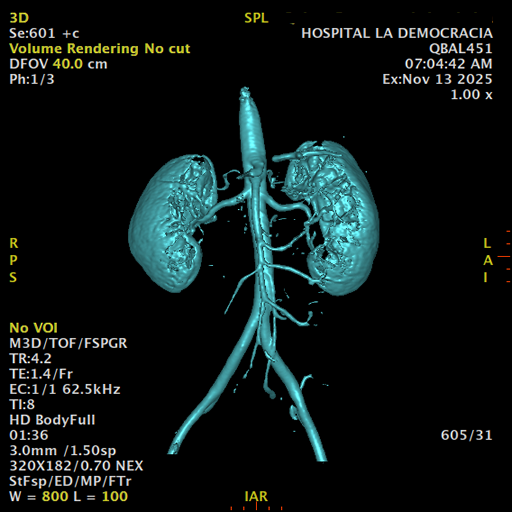

Paciente de sexo femenino, de 45 años de edad, refiere infecciones urinarias a repetición, no hay dolor, no refiere trauma, consulta por ardor al orinar, medico tratante le solicita resonancia abdominal, con énfasis en riñones, además un estudio de angiorenal.

Se prepara a paciente para ingreso a zona 4 del área de resonancia. Se coloca a paciente en decúbito supino, se canaliza en vena antecubital, se utiliza bobina de abdomen de 16 canales, se adquieren localizadores en tres planos, luego se procede a adquirir imágenes en diferentes planos, con secuencias echo spin y eco de gradiente, potenciadas a T1 y a T2.

Los sistemas colectores del riñón derecho y del riñón izquierdo, muestran alteración de sus calices primarios y secundarios, mostrando dilatación, la pelvis renal y el uréter se observan de características normales lo que indica que no hay proceso obstructivo.

Se observa dilatación del sistema calicial sin proceso obstructivo compatible con una anormalidad del desarrollo de los sistemas colectores de ambos riñones, definiéndose como una “megacaliosis”